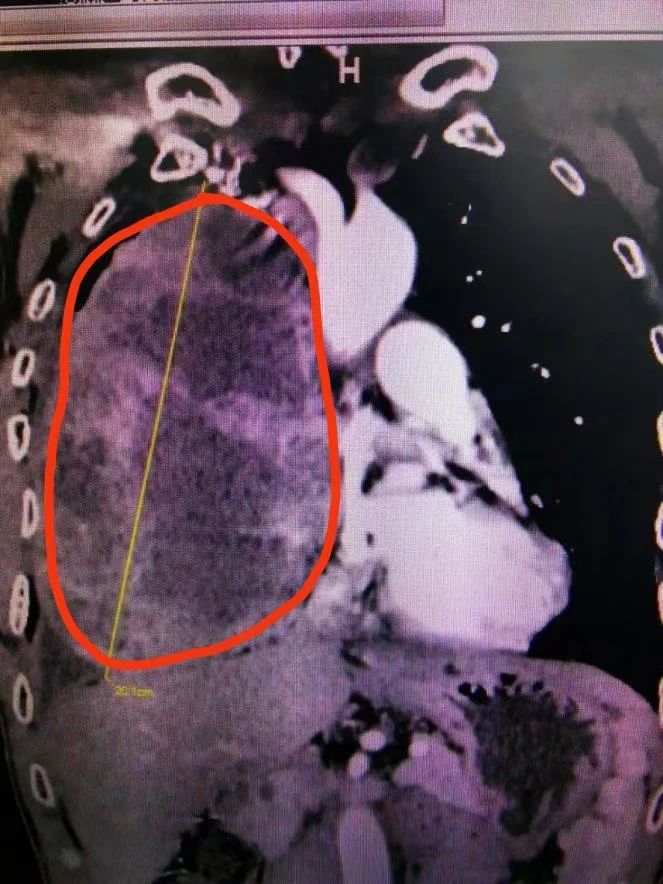

CT檢查(紅圈內為腫瘤)

實際上,李先生的情況確實比較棘手。鄧意平主治醫(yī)師表示,患者的胸部增強CT顯示前縱隔巨大腫瘤,因腫瘤巨大,腫瘤內滋養(yǎng)血管非常豐富,并累及右側胸腔大部,右肺受壓明顯;與心包、無名靜脈、上腔靜脈、右肺動脈等重要血管界限不清。

鄧意平主治醫(yī)師介紹,縱隔是一個解剖區(qū)域,位于兩肺之間,胸骨和胸椎為前后界。縱隔內原發(fā)腫瘤以良性多見,也有部分惡性。因其內有重要器官,原則上縱隔腫瘤一經發(fā)現,建議手術治療,對于直徑大于10厘米的腫瘤被稱之為巨大縱隔腫瘤,該患者的腫瘤達20多厘米的情況實屬罕見。